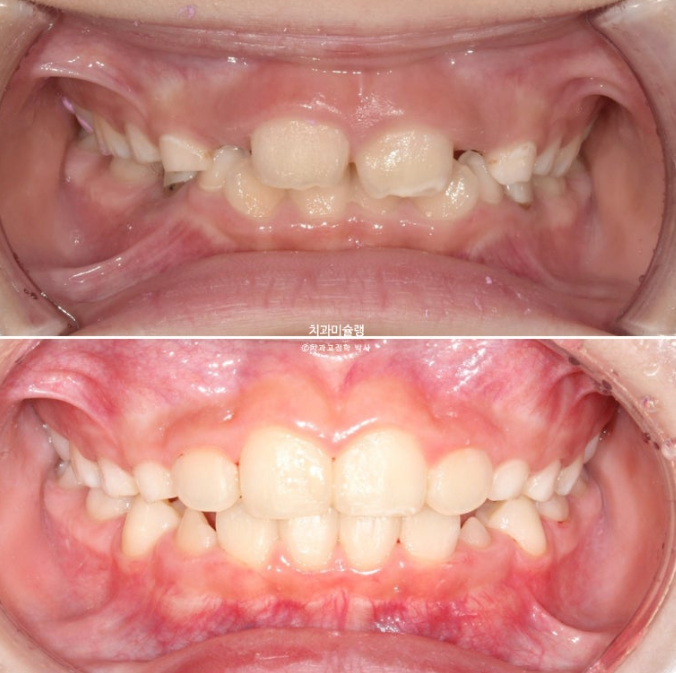

23년 10월, 교정치료를 위해 온 어린이 입니다.

앞니 두 개 높낮이 차이, 앞니가 깊게 물리는 과개교합이 보입니다.

앞니 네개 중 옆 앞니 즉 측절치가 나올 공간이 좁습니다.

아래도 마찬가지 입니다.

앞니가 벌써 삐뚤삐뚤 합니다.

송곳니가 나올때는 어떻게 될까요?

덧니 100% 예약입니다.

과개교합은 개선되었고 측절치 나올 공간을 악궁확장으로 미리 벌려줬기 때문에 측절치는 잘 내려왔습니다.

중심선은 잘 맞아졌고 과개교합은 더 개선이 되었습니다.

이제 전 후 비교 보겠습니다.

23.10~25.08